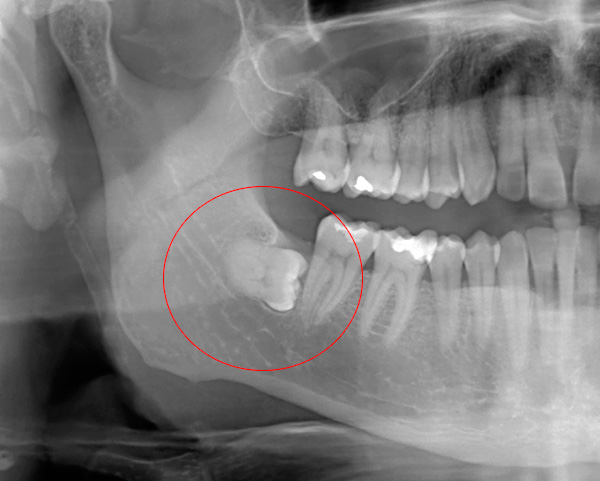

- L'opzione opposta: ci sono stati problemi con l'eruzione del dente del giudizio, cioè stiamo parlando del cosiddetto dente del giudizio retinato (nascosto nella mascella sotto la gomma), o circa semi-penetrato (parzialmente sfondando la gengiva, a volte con la formazione del cappuccio gengivale). Spesso è difficile rimuovere i denti del giudizio inferiori ed è relativamente costoso. Tuttavia, la rimozione di altri molari (sei, sette) sulla mascella inferiore non è sempre facile;

I denti trattenuti si trovano completamente sotto la gengiva o si trovano generalmente nel tessuto osseo: la loro rimozione ha sempre una maggiore categoria di complessità. È più facile e veloce rimuovere il dente che è nascosto solo dalla gomma, poiché in questo caso potrebbe non essere necessario ritagliarlo dall'osso e con l'aiuto degli elevatori è possibile staccare rapidamente dal foro.

Ma la rimozione di un dente ritardato, situato in profondità nell'osso mascellare, richiede quasi sempre molto tempo (da 30-40 minuti a 2-3 ore) e richiede abilità speciali e una grande esperienza dal dentista.Pertanto, il costo della rimozione di denti complessi e raffinati raggiunge in cliniche private fino a 25 mila rubli (anche se, naturalmente, non è difficile trovare lo stesso servizio del valore di circa 5 mila se lo si desidera).